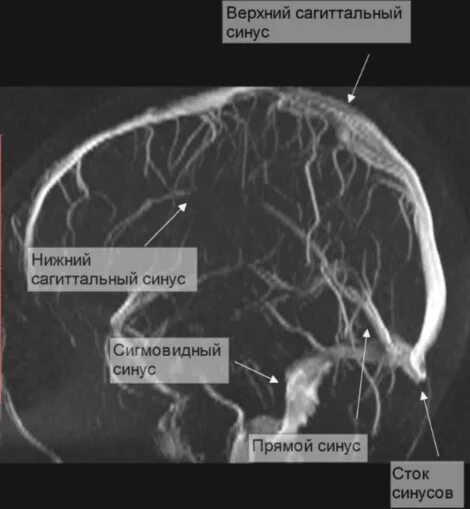

Синусы мозга мрт